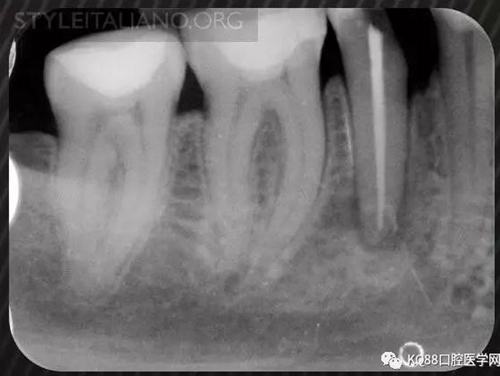

Img. 4 - Case 2: This necrotic first mandibular molar was treated in one visit, and the patient complained of post-operative pain. Analgesics and antibiotics were prescribed, and occlusion relieved. Symptoms disappeared after two days, and a radiographic follow-up after two years showed healing of the periradicular lesion.